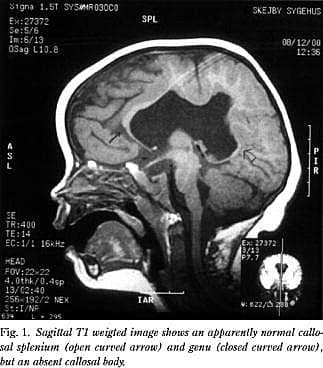

På grund af dysmorfologien og den forsinkede udvikling udførte man under anæstesi MR-scanning af cerebrum (Fig. 1 og Fig. 2 ). Scanningen afslørede et forstørret ventrikelsystem og septum pellucidum agenesia. Der fandtes mindre agenesi af begge temporalpoler. Corpus callosum var dysgenetisk med fraværende corpusdel. Der sås en sammenvoksning af den midterste del af de to storhjernehalvdele. Fissura sylvii fortsatte i en fissur frontoparietalt henover ventrikelsystemet og forbandt de to fissurer med hinanden. Der var ingen kortikale dysplasiforandringer eller heteropier. Der var normale myeliniseringsforhold og basalganglier. Billedet var foreneligt med middle interhemispheric fusion, også kaldet syntelencefali.

Synonymet middle interhemispheric fusion, skyldes den tilsyneladende sammenvoksning af den midterste del af hjernehalvdelene. Tilstanden betragtes som en mild form for holoprosencefali.